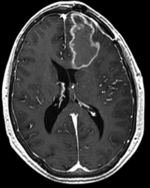

Registration Results

DTI deformation applied (before/after registration DTI deformation applied (before/after registration